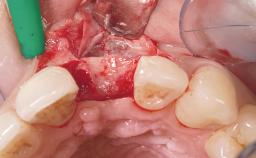

Early Placement of an Implant in a Maxillary Right Central Incisor Site

This 41-year-old female patient was referred to the clinic for the replacement of the right central incisor, since the tooth had developed a root fracture in the long axis that made extraction necessary. The healthy, non-smoking patient was first seen with the tooth still in place. A detailed Esthetic Risk Assessment was performed.The patient was worried about her dental esthetics and had high expectations for a successful treatment outcome from an esthetic point of view. The patient had a medium lip line that displayed parts of the gingiva in the anterior maxilla upon smile.

Bone Augmentation Horizontal|Simultaneous

Augmentation Materials Autogenous chips|Xenogenous|Membrane

Soft Tissue Anatomy Intact Defective

Bone Volume Deficient horizontally, allowing simultaneous augumentation

Soft Tissue Contour and Volume Slightly compromised